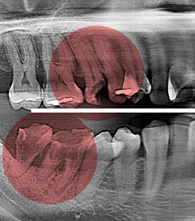

임플란트 누적 식립수[수술 성공률 98.1%]

18,576

Century Dental ClinicIt is conducted by a high-quality medical specialist..